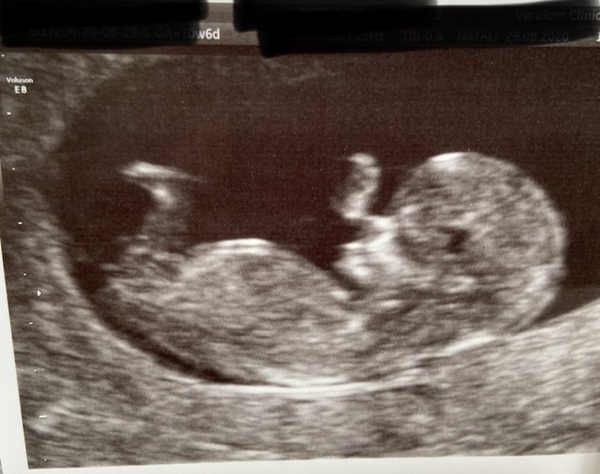

I had a private scan yesterday and measuring at 11w1, not long until I hopefully make it to the 12week mark 🤞 the sonographer was really nice and one of the first things she said was 'you may be feeling better now because placenta has completely taken over so less hormones surging though your system and all going to baby so don't panic it's a good thing' and then said that NT measurement from the scan would have me at low risk. Thought it was really kind for her to mention those things as think she could tell I was anxious x

Lovely pic @SmileyT ❤️ I really hope I can get the point of seeing a proper baby shape 🤞🏻❤️

Oh thats really lovely @SmileyT and congratulations! 💕 Great that she mentioned symptoms eating off. Did she tell you what your NT measurement was?

@SmileyT lovely scan picture! So glad it went well :)

@smileyt aww cute scan!

Very pleased, healthy baby at the scan today. Was so relieved. Private scan so my husband was allowed in too. LMP would be 10+6 but measured 11+2.

Two beautiful scans! Congratulations guys 😄 xx

@PhotoMum4 think we will probably end up due date buddies on the 18thish of June, congrats on a successful scan 🥳 I've only told 3people so far, I've not even let myself think about going 'public' but I reckon it's still a couple months off x

@SmileyT Congrats on the super successful scan! Sounds like your sonographer was lovely, too! Almost at the 12 week mark! 🥳

@PhotoMum4 Yay, congrats on your scan and double yay to measuring ahead - that's the dream! Have fun/hope you had fun telling the family 💕

Congratulations to the ladies with the lovely scans! I love seeing them.